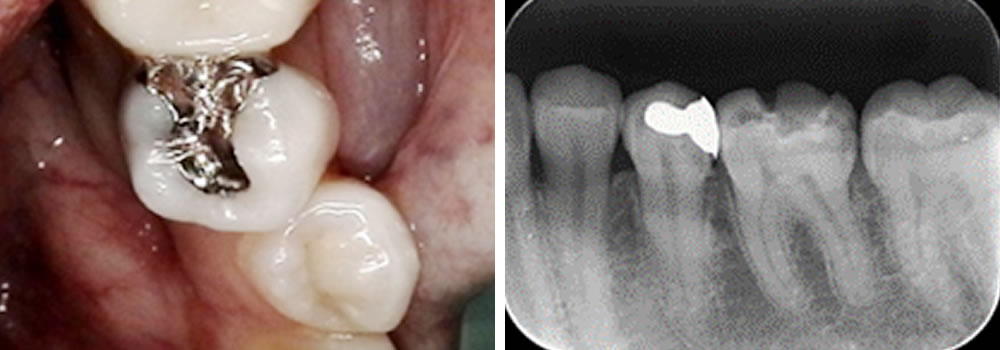

銀歯の虫歯治療後にセラミックで修復した症例

銀歯の虫歯治療後にセラミックインレーで修復した症例 こちらの患者さまは検診希望で来院されました。レントゲンをお撮りして口腔内を確認すると、左下前から数えて5番目の詰め物の下にむし歯の進行を確認しました。 保険のつめ物の除 […]